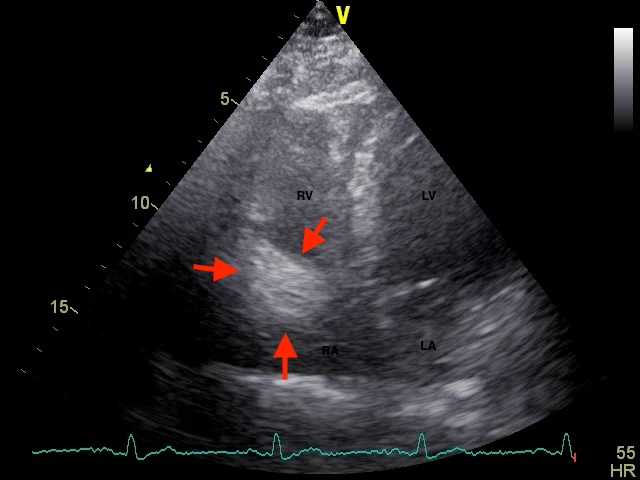

Figure 1. Four-chamber view on trans-thoracic echocardiogram showed a large cardiac pseudo-tumour (red arrows) at the right atrioventricular groove. RV = right ventricle, RA = right atrium, LV = left ventricle, LA = left atrium.

The patient was a 74-year-old Chinese male who presented with left hemiparesis due to intra-cranial haemorrhage in the right thalamus. He had history of hepatitis B carrier status, bronchiectasis and hyperlipidaemia. He was referred for echocardiogram, which showed a large solid-looking “tumour” mass (2.2 × 2.3 cm) in the right atrioventricular groove with mass effect (Figure 1). Magnetic Resonance Imaging scan of the heart showed a concentric mural lesion (measuring 3.2 × 2 × 2.3 cm) encasing the mid-to-distal right coronary artery (RCA) and a similar but smaller concentric mural lesion encasing the mid-left anterior descending artery (LAD). Computed tomography (CT) coronary angiogram showed non-obstructive coronary artery disease with multiple segments of concentric mural thickening around the RCA, LAD, diagonal artery and left circumflex artery (LCx), compatible with coronary arteritis. The largest lesion at mid-distal RCA had the appearance of a “pig-in-a-blanket” (Figure 2). Serum IgG4 level was grossly elevated at 9.85 g/L (normal range 0.04 - 0.86 g/L). The diagnosis of IgG4 coronary arteritis was made. Further assessment of the extent of the disease was performed by PET/CT scan with 18F-fluoro-deoxy-glucose (FDG) and 68Ga-Fibroblast Activation Protein Inhibitor (FAPI) tracers. PET/CT demonstrated mild 18F-FDG and 68Ga-FAPI activity at the soft tissue densities along the LAD, RCA and LCx, suggestive of inflammation along the coronary arteries (Figure 3). A small 68Ga-FAPI-avid focus at pancreatic head, suggestive of same disease involvement, was not detectable by 18F-FDG scan. While the 18F-FDG scan showed mild grade activity along the ascending and descending thoracic aorta and lymph nodes (non-specific findings), activity was not detectable on the 68Ga-FAPI scan. Bone marrow aspirate was normal and did not show any increase in plasma cells. Despite the lack of symptoms, treatment was indicated to prevent the progression of IgG4-RD in the heart and other major organs. In view of his hepatitis B carrier status, it was decided not to give him glucocorticoid therapy. He was given 8 doses of intravenous rituximab (an anti-CD20 antibody) at 375 mg/m2 weekly for 4 doses followed by 375 mg/m2 once every 2 months for 4 more doses with good serological response (Figure 4). He had good recovery from his stroke and remained free from any cardiac symptoms. Repeat CT coronary angiogram after the rituximab therapy showed similar mural thickening around the coronary arteries with no change in the size of the largest pseudo-tumour around the RCA.